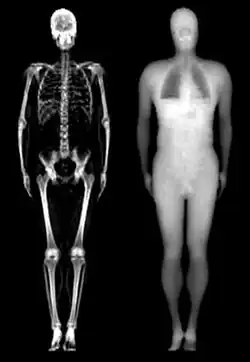

Während bei herkömmlichen digitalen Röntgenverfahren lediglich eine Röntgenquelle eingesetzt wird, setzt das Dual-Röntgen-Absorptiometrie-Verfahren (engl. dual-energy X-ray absorptiometry, DXA oder DEXA) gleichzeitig zwei energetisch leicht unterschiedliche Röntgenquellen ein. Materialien mit unterschiedlicher Dichte zeigen in Abhängigkeit von der Energie der Röntgenstrahlung unterschiedliche Schwächungscharakteristiken. Für jeden Messpunkt im Röntgenbild existieren also beim DEXA-Verfahren zwei Schwächungswerte für die zwei eingesetzten Röntgenstrahlenergien. Dementsprechend können im Vergleich zum herkömmlichen Röntgenverfahren nicht nur die allgemeine Schwächung durch den gesamten Körper gemessen, sondern auch verschiedene Materialien genauer unterschieden werden.[2] Wichtig hierfür ist ein möglichst großer Unterschied der jeweiligen Dichte.

Beim Einsatz am Menschen werden dabei drei Gewebearten unterschieden: Knochen-, Muskel- und Fettgewebe. Es stehen jedoch nur zwei Messwerte zur Verfügung. Um zwischen diesen zu unterscheiden, müssen zusätzliche Annahmen getroffen werden, die je nach Anwendungsgebiet zu mehr oder weniger großen Messfehlern führen.[3] Das DXA-Verfahren eignet sich beispielsweise zur Bestimmung der Körperzusammensetzung aus Knochen-, Fett- und Muskelmasse. Es liefert keine Information über die dreidimensionale Geometrie des Messobjektes und somit keine Dichtewerte im physikalischen Sinne (SI-Einheit der Dichte: kg/m³), sondern eine flächenprojizierte Masse (SI-Einheit: kg/m², auch als Flächendichte bezeichnet).